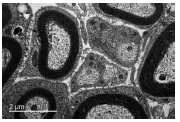

Las fibras nerviosas mielínicas se identificaron gracias a las características de su vaina de mielina, al microsco- pio óptico, y como se muestra en la figura 1 se aprecian diferencias considerables en su tamaño. El diámetro de la fibra (figura 3) y el espesor de la vaina de mielina en el grupo E presentaban una distribución bimodal en los histogramas. Por su parte, las demás variables de este grupo presentaron una distribución unimodal. Respecto de todas las variables en los otros grupos, su distribución fue unimodal. Las fibras, independientemente de su tamaño, se encuentran repartidas al azar en toda la sección del nervio. Los resultados obtenidos mostraron que los nervios aumentaron su área media con la edad, siendo para el grupo A significativamente menor que para los grupos C, D y E (P ≤ 0,05). Es interesante señalar que el valor de esta variable fue 4,25 veces mayor en el grupo E que enel grupo A (cuadro 1).

Light micrograph of transverse section (40x) of the oculo- motor nerve in group E. Differences in size of myelinated fibres can be observed

Las fibras amielínicas, con morfología ovalada o redondeada, se identificaron mediante el uso de microscopia electrónica en todos los nervios de los cinco grupos de edad estudiados. Como se muestra en la figura 4 presentaban tamaños variados, y se encontraban distribuidas entre las fibras mielínicas.